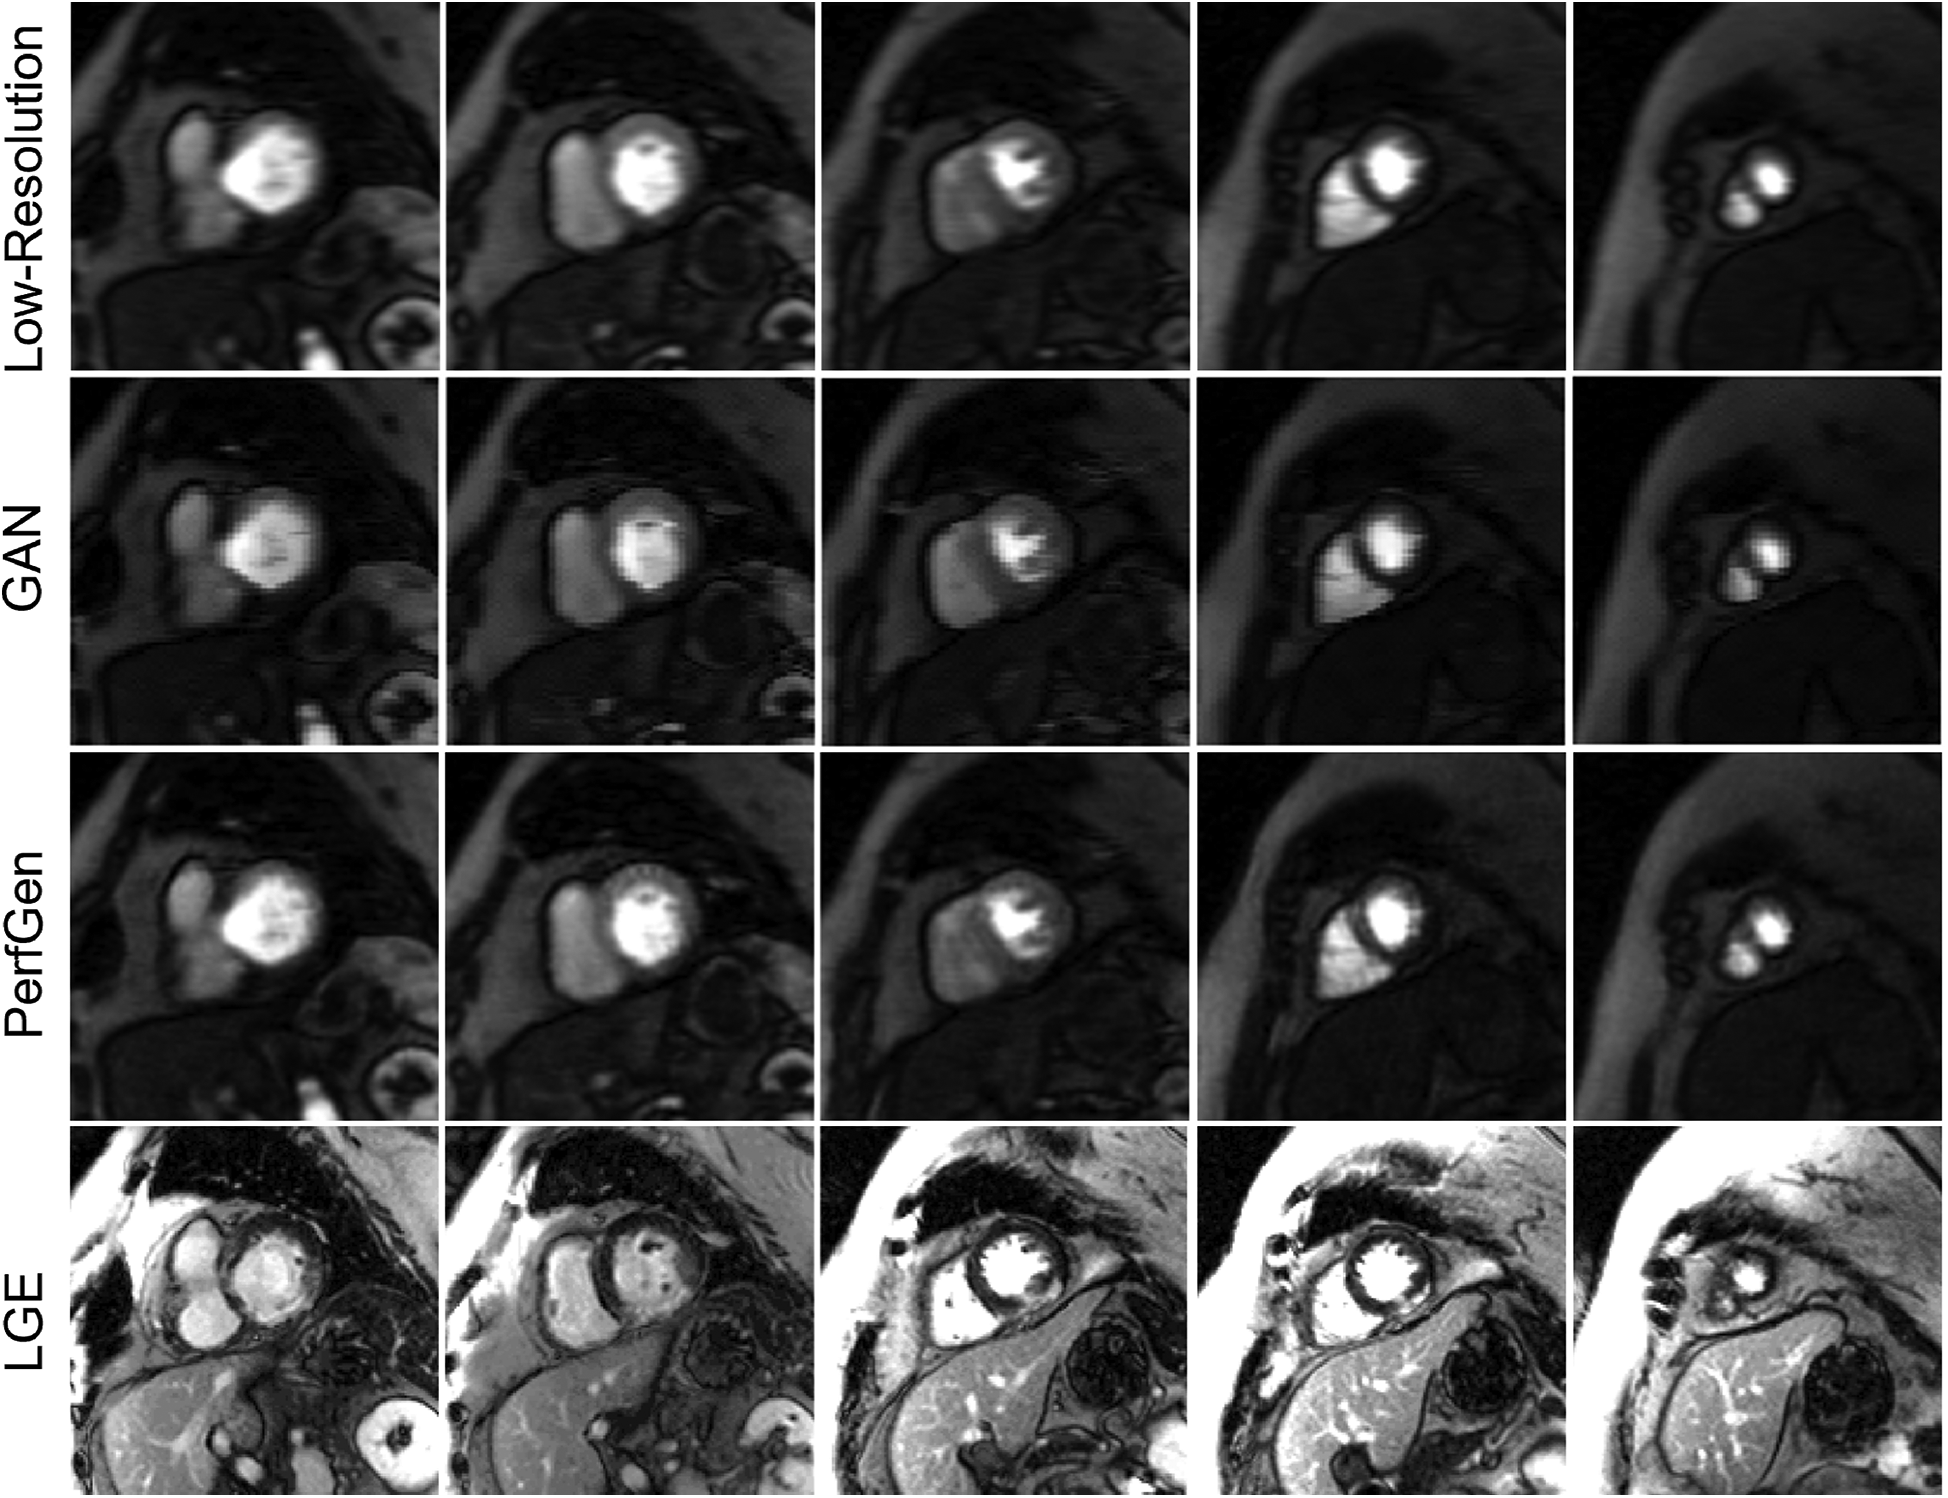

Figure 8 compares the super-resolved perfusion images by PerfGen and GAN to both LR perfusion images and LGE images. The super-resolved images show perfusion defects that closely match the defects observed in the LGE images at corresponding slice locations, providing proof-of-concept that PerfGen can potentially identify the super-resolve perfusion defects from LR images. PerfGen demonstrates better alignment with LGE compared to GAN-based super-resolved perfusion images. Furthermore, the combination of a LR acquisition with 35% phase lines and GRAPPA-2 allowed the acquisition of five slices, with a 2.86-fold improvement in temporal resolution compared to clinical routine settings, demonstrating the improved image quality with improved slice coverage.

Figure 8

Comparison of low-resolution (LR), GAN super-resolved images, PerfGen super-resolved images and LGE images for one prospectively acquired myocardial perfusion dataset. The first row illustrates the LR perfusion images, followed by the super-resolved images by GAN and PerfGen. The last row shows the corresponding LGE images at similar slice locations. The PerfGen super-resolved perfusion images highlight perfusion defects that match the locations of defects observed in the LGE images. PerfGen demonstrates superior alignment with LGE compared to GAN-based super-resolved perfusion images, demonstrating the ability of PerfGen to recover and enhance important diagnostic features. This figure also shows how the combination of LR acquisition of 35% phase resolution and GRAPPA-2 can improve slice coverage, with five slices acquired and 2.86-fold higher temporal resolution for this patient.